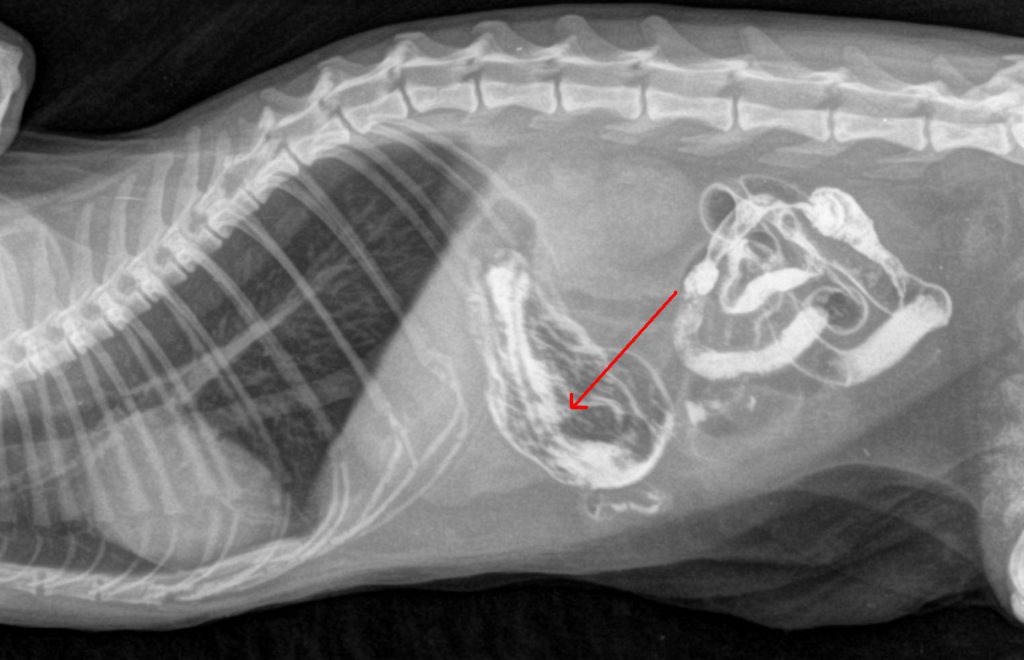

Рентгеновские снимки головы кошки в боковой проекции